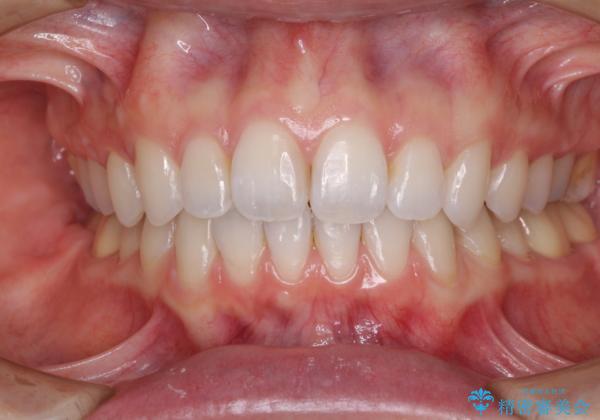

深い咬み合わせと奥歯のむし歯 総合歯科治療

- 奥歯の虫歯と前歯のデコボコや突出感を気にして来院された患者様です。

上顎歯列が、下顎に対して前方にありましたが、口元に出っ歯の印象がなかったため、親知らずを抜歯した上で、上顎歯列全体を後方に移動させることとしました。

咬合力が強いため、アンカースクリューを使用し、ワイヤー装置にて矯正治療を行うこととしました。

矯正治療後は、奥歯の虫歯や銀歯を補綴・修復治療することとしました。

上顎歯列を下顎に対して4mmほど移動させる必要があったため、治療は長期化することが予想されましたが、患者様にはこちらの期待以上にゴムかけなどに協力いただき、補綴治療も含めて2年強で終えることができました。